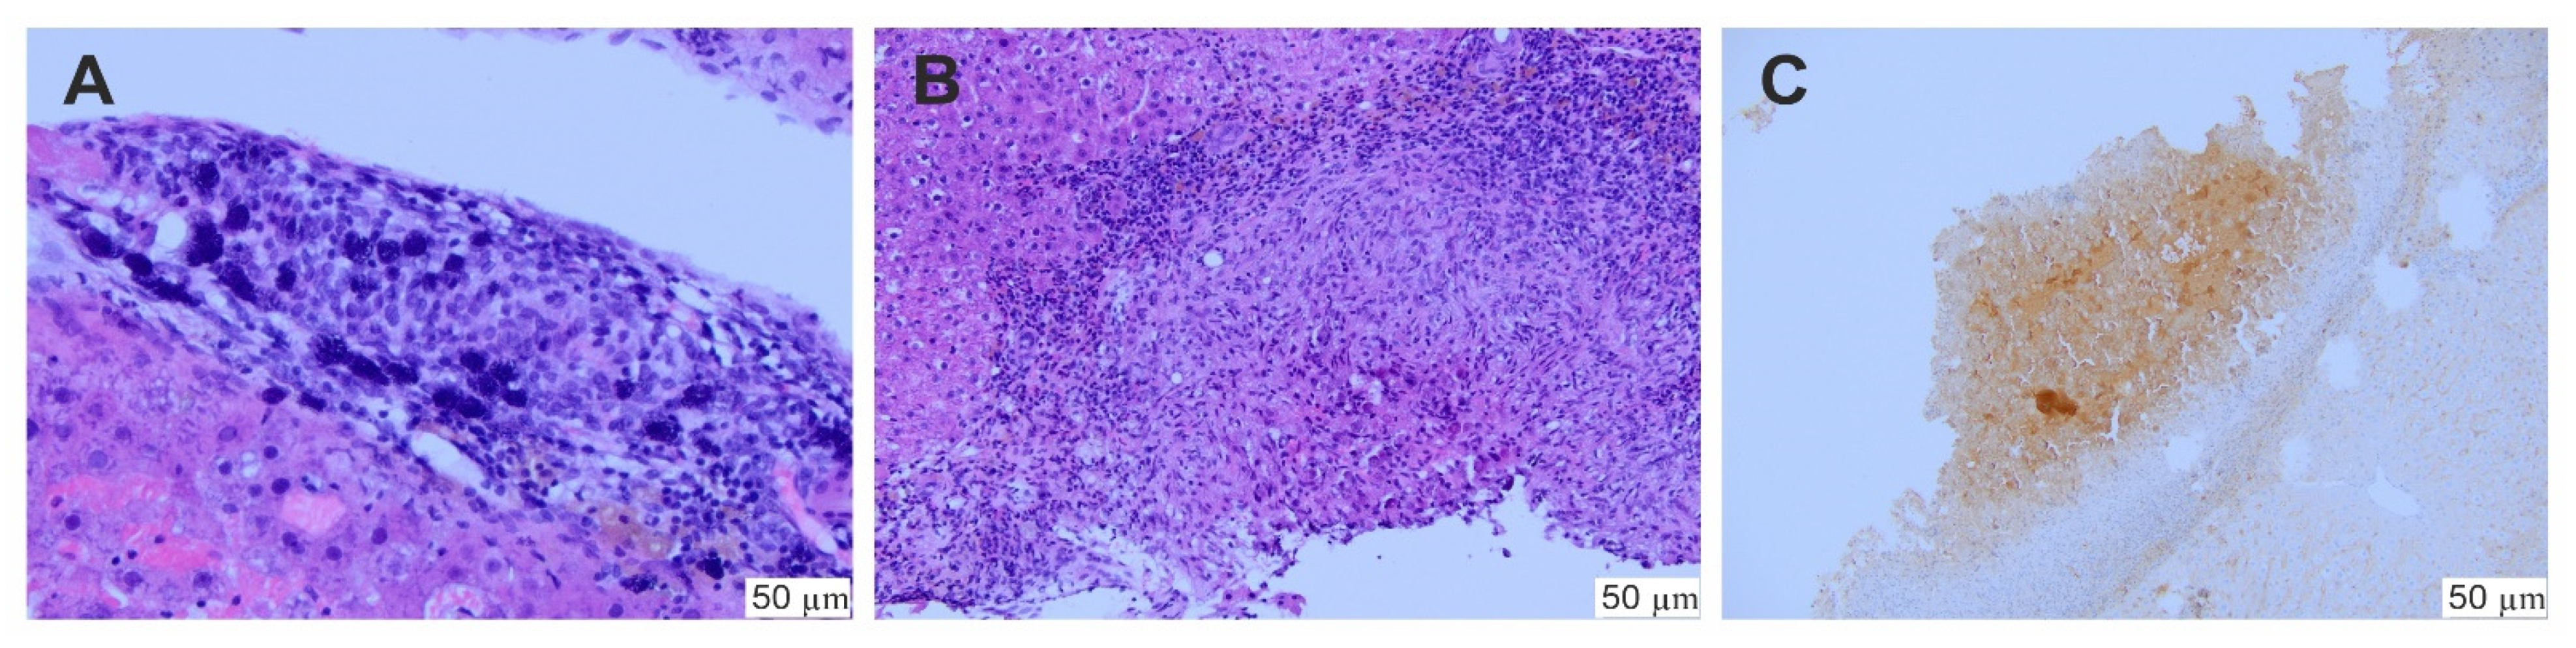

In the whole in vivo study group (45 rats), the implantation of the hepatoma cells was successful and the presence of tumor was histologically confirmed (Figure 7). Then, SOR alone or two types of SOR nanocarriers (SR-SOR@PPF and FR-SOR@PPF) were implemented. After the second surgery, one rat from the placebo group died due to massive bleeding as a consequence of the sparing resection (which was diagnosed post-mortem). Besides, there were no other incidents which affected the health of the animals. No abnormal changes in behavior were observed, and no additional treatment was administered. None of the other animals have been disqualified from the study. The mean tumor size after the treatment was 3.64 (± 0.24) mm, 2.62 (± 0.27) mm and 1.73 (± 0.36) mm in the C, SR and FR groups, respectively. Animals treated with SR-SOR@PPF and FR-SOR@PPF demonstrated significantly lower tumor size at the end of the study. The outcome was slightly improved, compared to the control, among the FR-SOR@PPF group (p = 0.004) than the SR-SOR@PPF (p = 0.043) (Figure 8A,B).

Figure 7. Histological assessment of the biopsy. (A) Hepatoma cells, (B) a minor tumor with severe fibrosis and inflammation; (C) hepatoma confirmation—immunochemical reaction for alpha-fetoprotein.